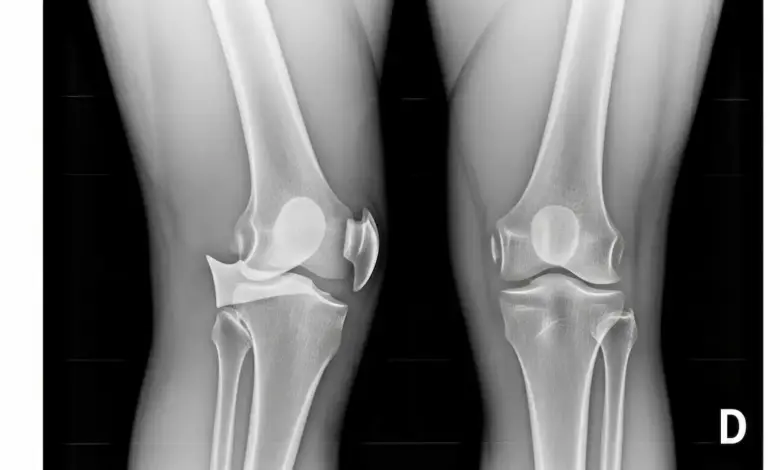

A radiografia em pé é um dos exames mais importantes. Ela mostra o eixo da perna e ajuda a medir o grau do desvio.

Esse exame também ajuda a diferenciar a doença de Blount de outras causas de perna arqueada, como varo fisiológico, raquitismo e outras alterações do crescimento.